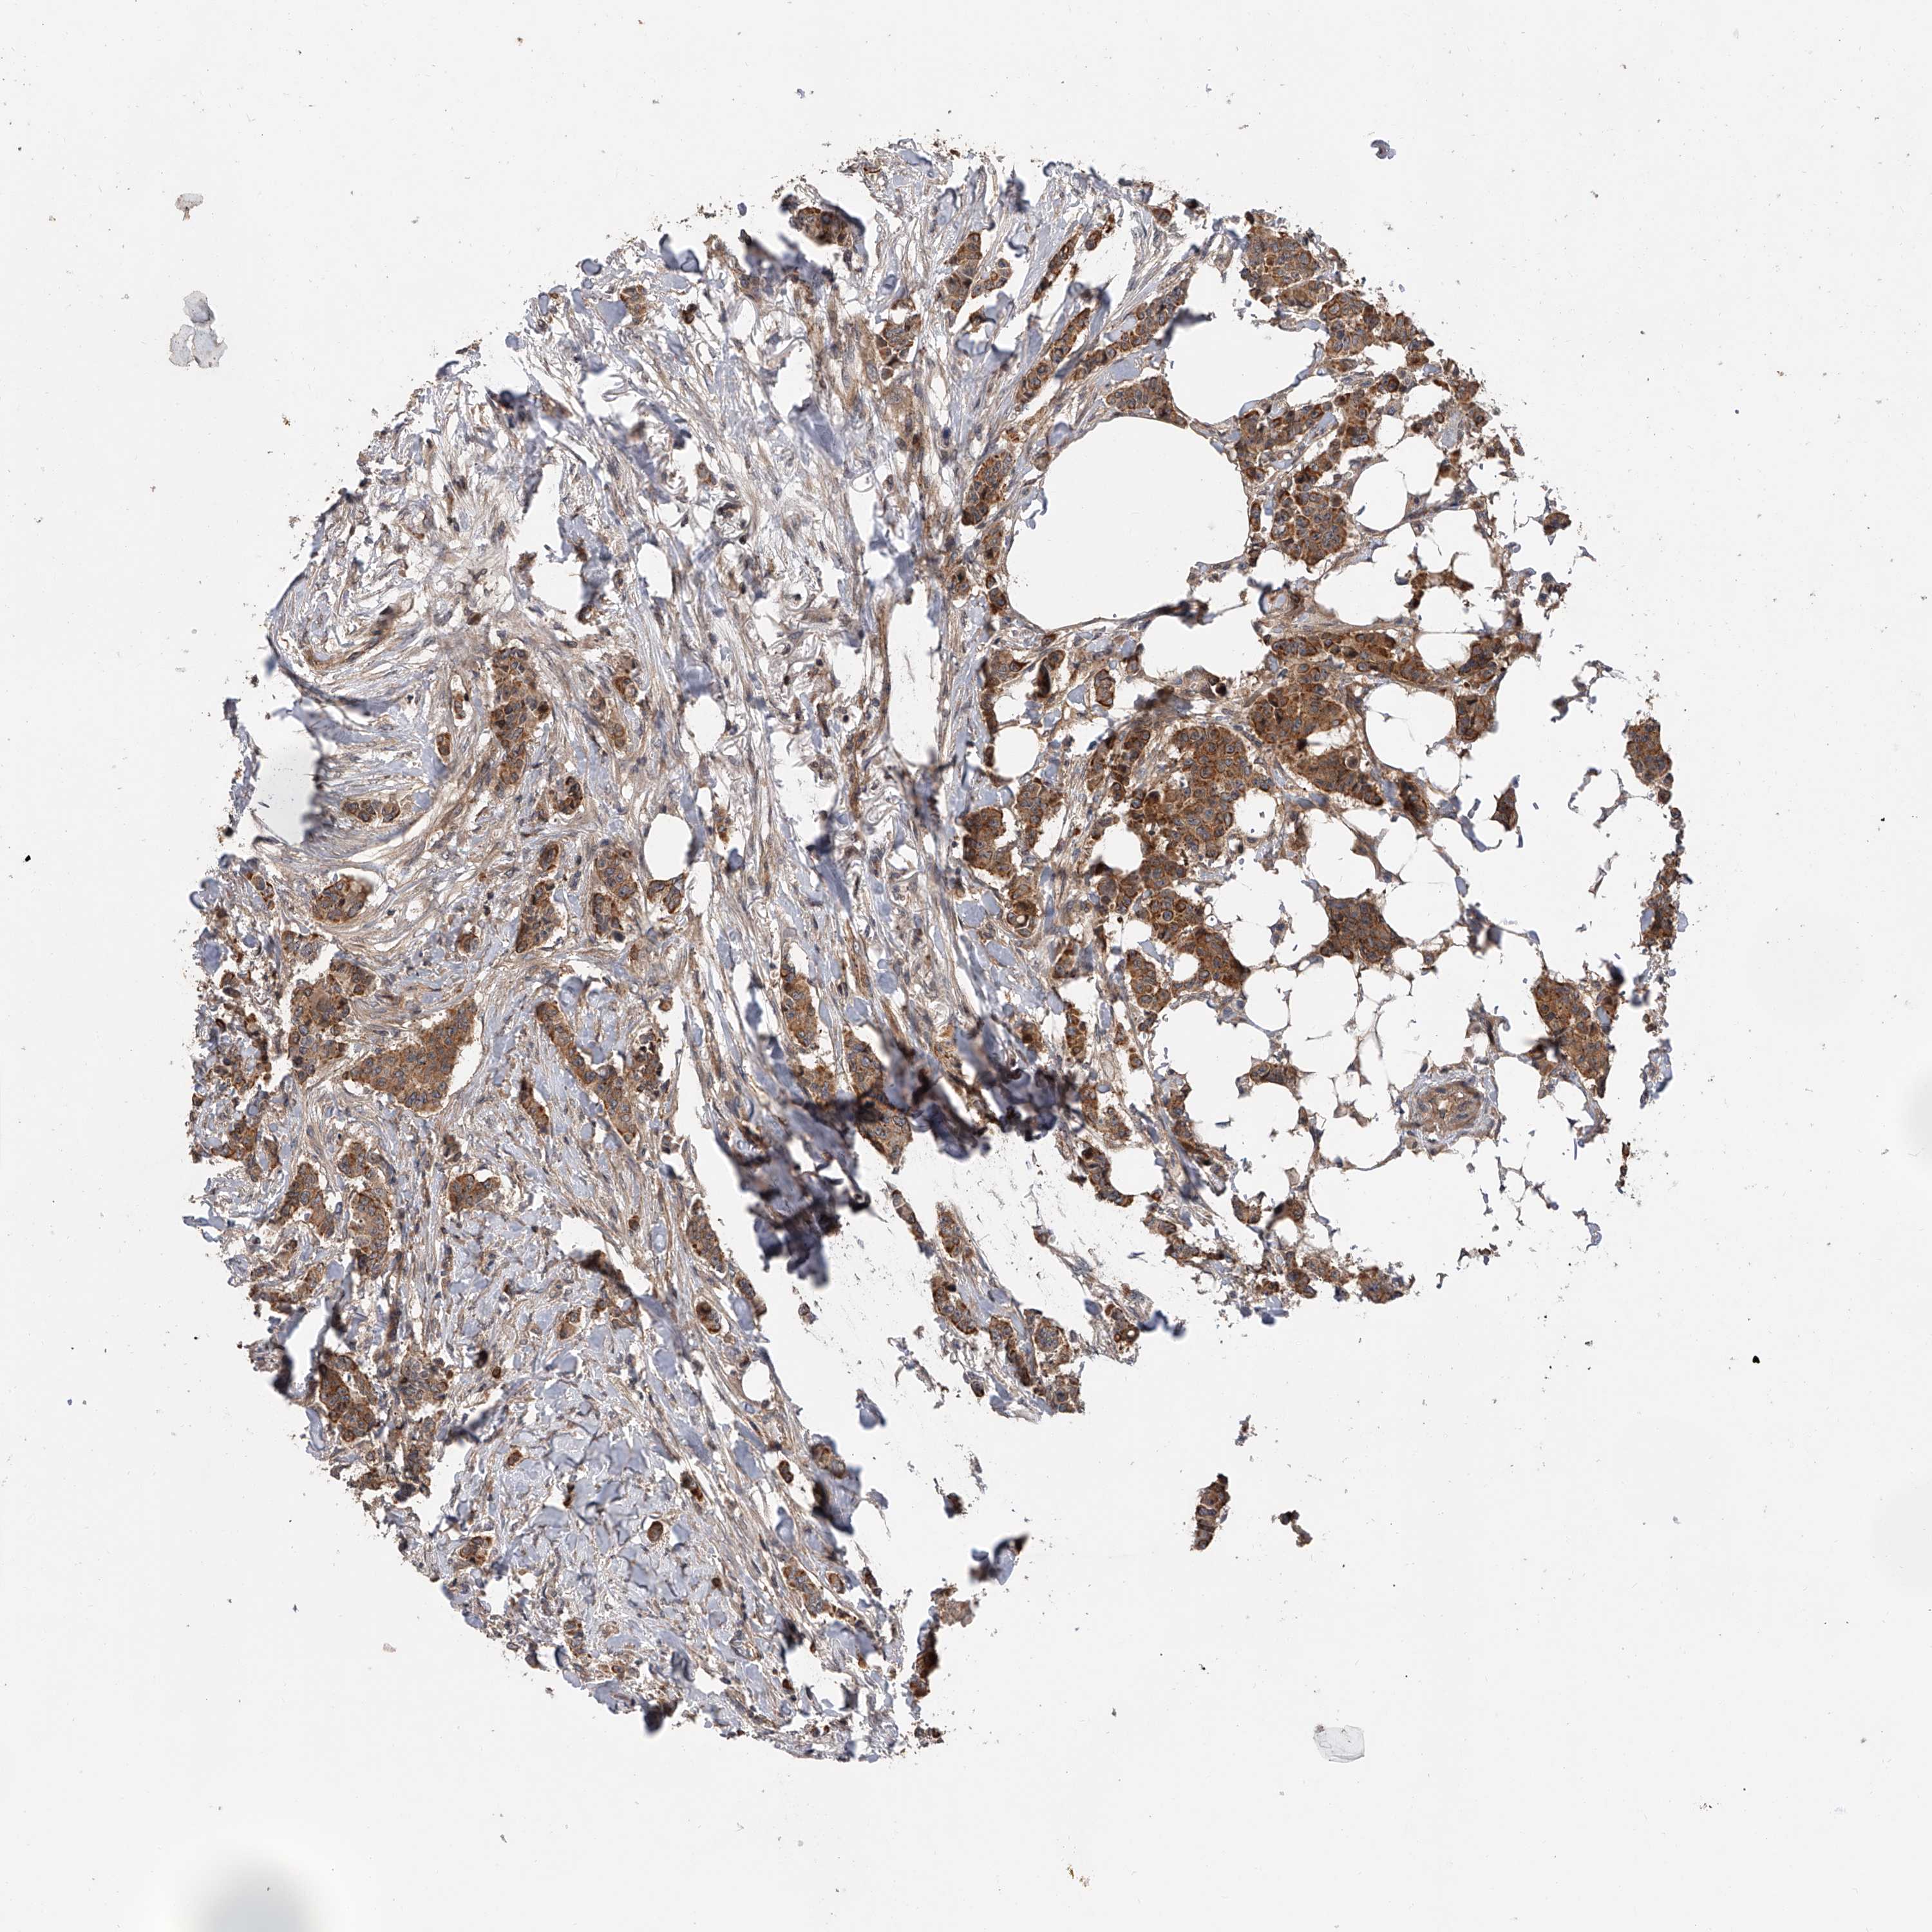

CANCER BREAST CANCER Show tissue menu

BRCA TCGA BRCA VALIDATION PROTEIN EXPRESSION

Breast cancer

Human cancer